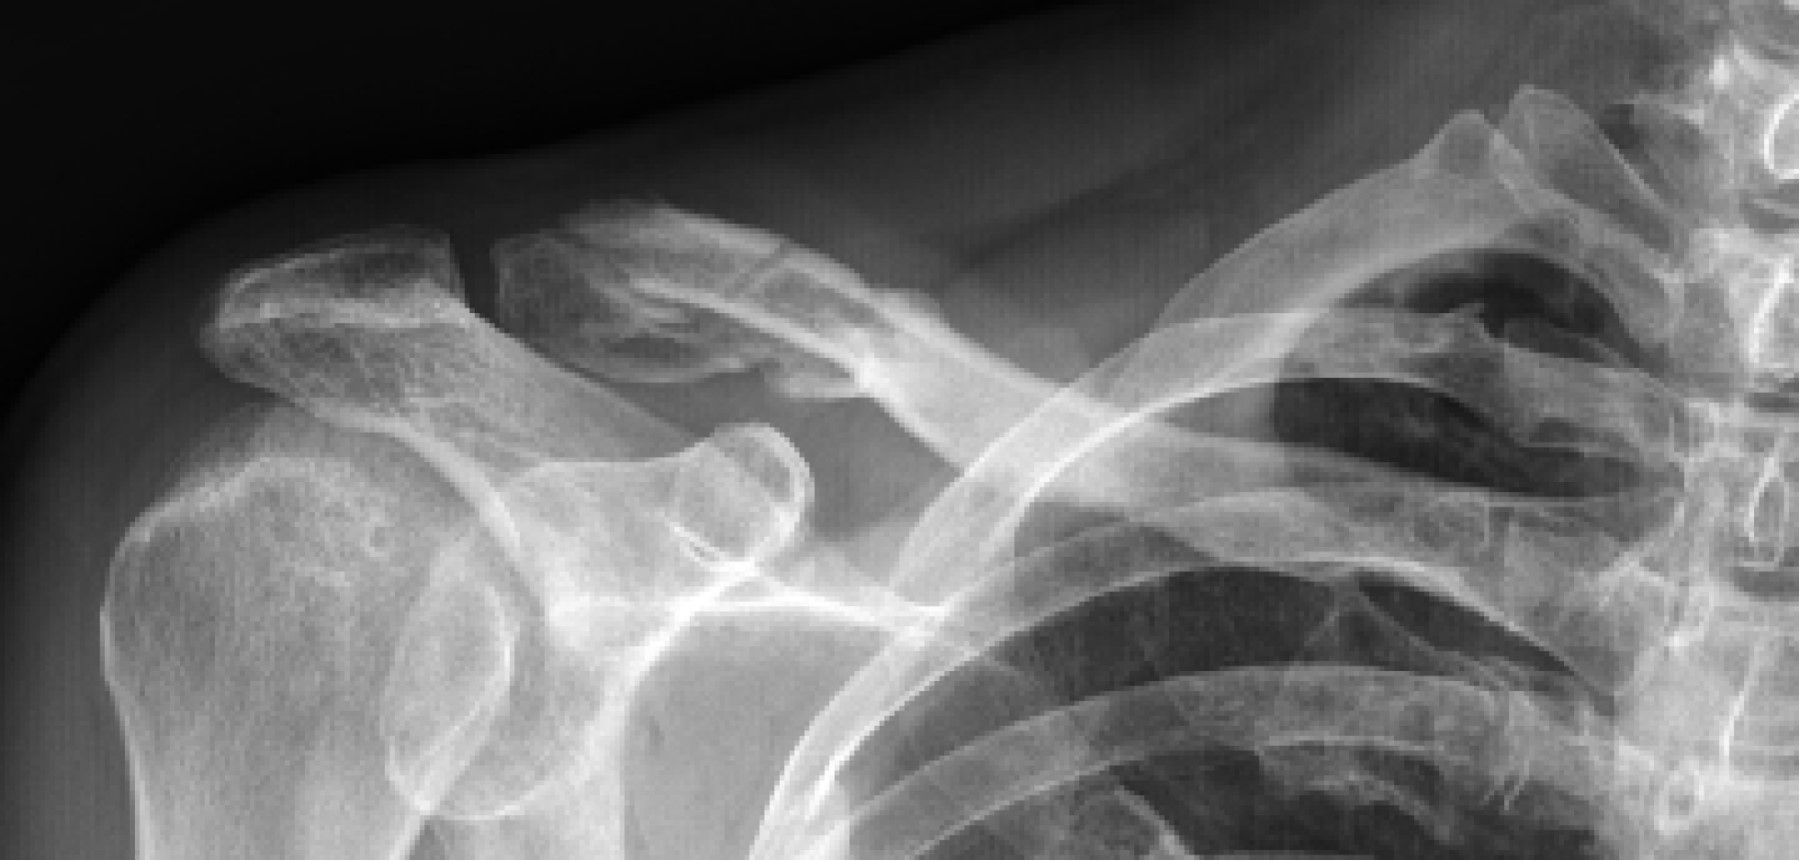

En todos los casos se obtuvo la consolidación ósea sin incidencias (Figura 3) y todos los pacientes quedaron satisfechos con el resultado estético (Figura 4). A los seis meses de seguimiento postoperatorio, todos habían reanudado sus actividades previas a la lesión, incluida la actividad deportiva. Al año de la lesión, la puntuación media en el cuestionario de la American Shoulder and Elbow Surgeons (ASES) fue de 85.5 puntos (rango: 83.3-88.3) y la puntuación media del cuestionario Disabilities of the Arm, Shoulder and Hand (DASH) fue de 7.5 (rango: .4.5-11.4). No se observaron complicaciones y todos los pacientes refirieron encontrarse satisfechos con el resultado.

Figura 3